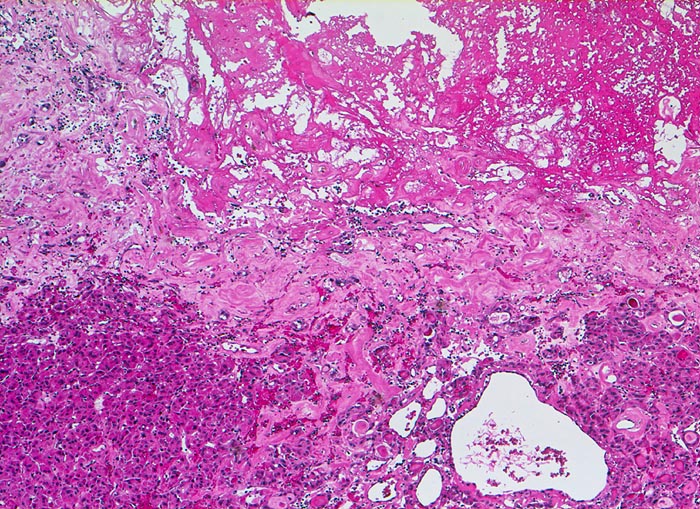

follikuläres Schilddrüsenkarzinom

Ausschnitt aus dem Tumor mit Fibrose und Einblutung (oben im Bild)

Seit zirka 10 Jahren ist beim Patienten eine Struma bekannt. Jetzt sucht er den Hausarzt auf, weil er den Eindruck hat, die Schilddrüse sei grösser geworden. In der Ultraschall-Untersuchung wird ein Knoten im rechten Schilddrüsenlappen festgestellt, der relativ scharf vom angrenzenden Gewebe abgesetzt ist. Die Feinnadelpunktion ergibt eine follikuläre Neoplasie; eine Unterscheidung zwischen einem follikulären Adenom und einem follikulären Karzinom ist zytologisch jedoch nicht möglich. Es wird eine Hemithyreoidektomie durchgeführt und nach der Diagnosestellung eines follikulären Karzinoms eine Resthyreoidektomie angeschlossen.

Histologie

50